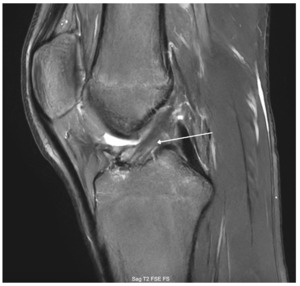

A 15-year-old male weighing 150 pounds and standing 6 ft 1 in tall, with no past medical history, presented to the clinic with buckling, catching and locking of the medial knee. He is a high school athlete who sustained a non-contact injury involving knee flexion combined with external rotation during a football game. He immediately reported a pop in the knee followed by stiffness and swelling. Clinical examination revealed joint effusion and medial and lateral joint line tenderness, on the inferior pole of the patella and tibial tubercle. Passive range of motion was limited, and both Lachman and McMurray tests were positive. Radiographs confirmed open physes with no evidence of fracture or malalignment., MRI demonstrated bony contusions and a substantial ligament injury, with a high-grade partial ACL tear, along with questions of peripheral posterior medial meniscus root tearing (Figures 1, 2). Management options were discussed with the patient, and he elected to proceed with surgical fixation. An additional consent was obtained from parental guidance for the possible publication of the surgical technique.